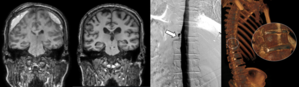

고대 구로병원 허윤정 교수팀, '외상성 대량출혈 환자, 연령별 대동맥 직경 예측 인자 규명'